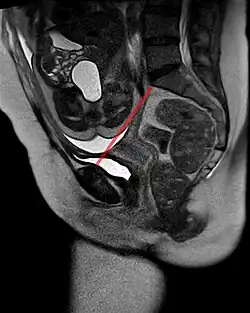

- Streckung. Der Kopf muss nun durch einen Knick im Geburtskanal treten. Dazu stemmt er sich am Symphysenrand an und gelangt so in eine Streckhaltung. Das Hinterhaupt erscheint unter der Symphyse. Beim sog. Einschneiden treten Scheitel, Stirn und Kopf durch den Damm.